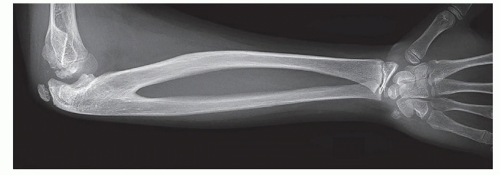

Complete radioulnar congenital synostosis (Figure 13.1)

![]() Figure 13-1 ▪ Lateral x-ray showing complete radioulnar synostosis with embedded radial head. (Courtesy of Children’s Orthopaedic Surgery Foundation.) |